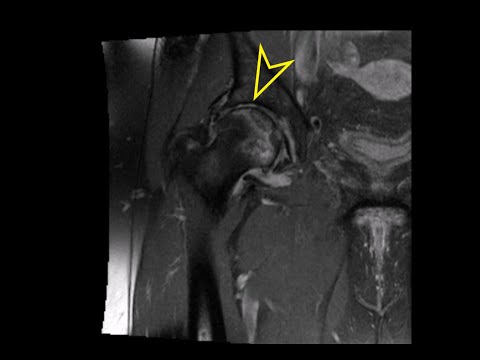

Hip MRI: Avascular Necrosis